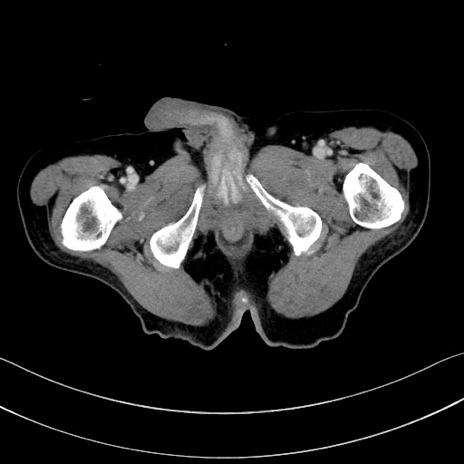

症例28(横断像)

【症例】60歳代男性

【現病歴】胃癌にて胃全摘後。食思不振が悪化し、夜中に嘔吐することがある。

【既往歴】胃癌、胃全摘、脾摘、胆摘後